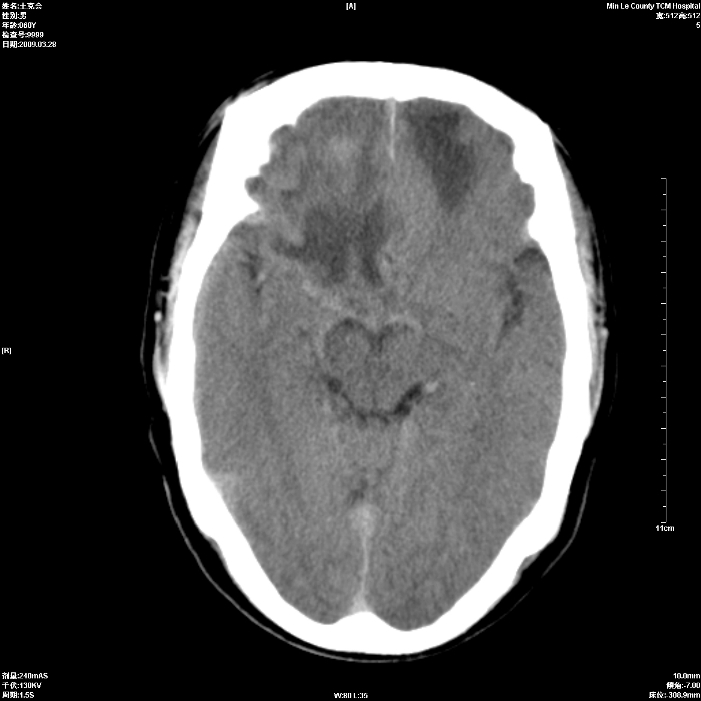

标题: CT19074:患者男60岁头晕头痛一月, [打印本页]

标题: CT19074:患者男60岁头晕头痛一月,

考虑额叶脑转移瘤,建议ct增强

考虑双侧额叶脑转移瘤;建议行进一步检查。

双侧额叶转移瘤

占位征像加水肿带,建议ct增强。

双侧额叶均有低密度影,考虑:1、嗅沟脑膜瘤。2、转移瘤。 建议增强扫描进一步检查。